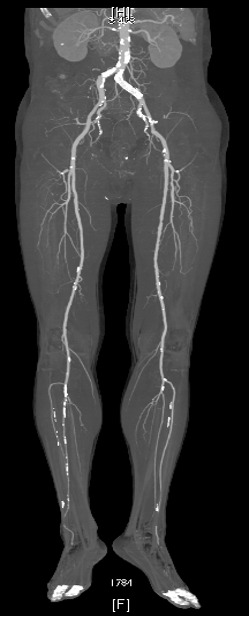

CTA:左侧股总动脉高钙化性偏心性严重狭窄病变,左股浅动脉及腘动脉全程弥漫性钙化病变,节段性狭窄,股浅动脉远段至腘动脉P1段完全闭塞,左侧胫前动脉至足背动脉闭塞

ABI:左侧0.37,右侧0.81

根据PACSS 透视/DSA下钙化分级属于PACSS Grade 4C

下肢动脉CTA提示左股腘动脉通畅,DES区域未见内膜增生管腔丢失表现